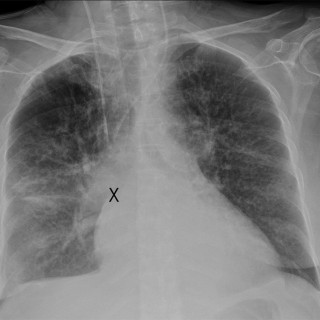

Bevissthetsforstyrrelser kan ha mange forklaringer, og av og til blir enkle årsaker oversett. Vi forteller her om en ung turskiløper som utviklet en alvorlig indremedisinsk tilstand med dramatiske symptomer. Ikke før betydelige prehospitale ressurser var satt inn og mannen ble undersøkt på sykehus, viste det seg at tilstanden kunne vært enkel å behandle. En mann i slutten av 20-årene var på skitur i fjellet sammen med venner. Været var fint, men snøen var våt og tung, og skituren, som varte i syv timer, ble mer strabasiøs enn de først hadde tenkt. Like før de kom frem til bestemmelsesstedet...